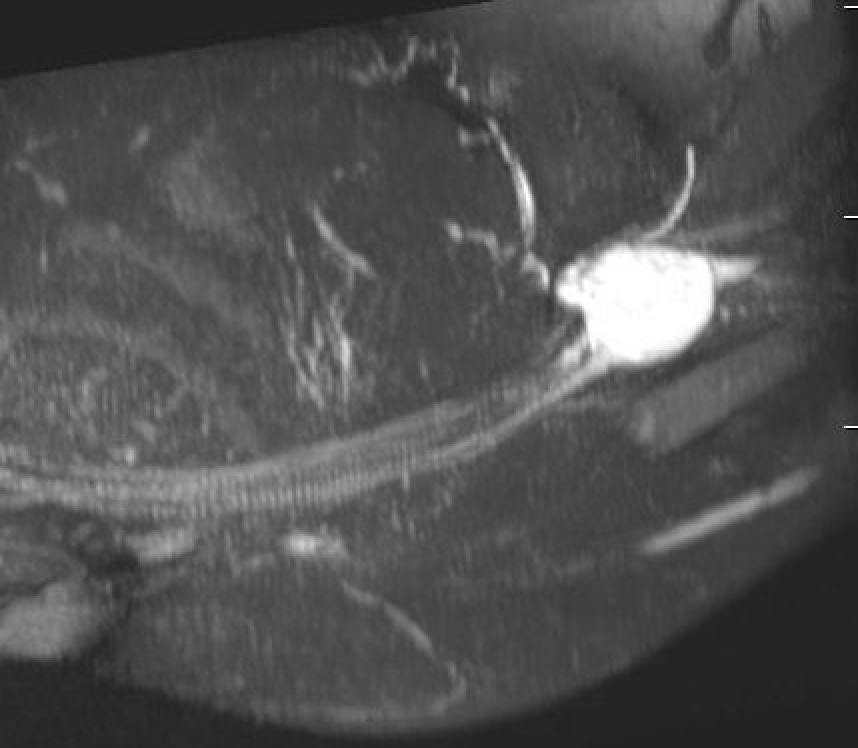

MRI

Target sign

- hypointense centrally

- hyperintense peripherally

Neurofibroma median nerve